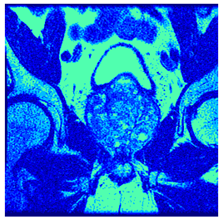

| Image | nt = 3 | nt = 4 | nt = 5 | nt = 8 |

|---|---|---|---|---|

| 1 | ![]() | ![]() | ![]() | ![]() |

| 2 | ![]() | ![]() | ![]() | ![]() |

| 3 | ![]() | ![]() | ![]() | ![]() |

| 4 | ![]() | ![]() | ![]() | ![]() |

| 5 | ![]() | ![]() | ![]() | ![]() |

| 6 | ![]() | ![]() | ![]() | ![]() |

| 7 | ![]() | ![]() | ![]() | ![]() |

| 8 | ![]() | ![]() | ![]() | ![]() |

| 9 | ![]() | ![]() | ![]() | ![]() |

| 10 | ![]() | ![]() | ![]() | ![]() |

| 11 | ![]() | ![]() | ![]() | ![]() |